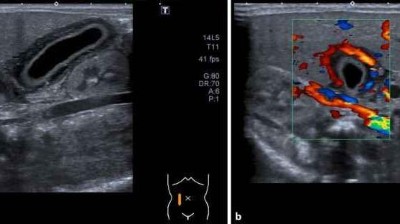

Beratungsgespräch/© lithiumphoto / stock.adobe.com (Symbolbild mit Fotomodellen), Sonographien Ureteropelviner Stenosen/© Dr. Kammer / LMU München (mit freundlicher Genehmigung), Frau wird Blut abgenommen/© andresr / Getty Images / iStock (Symbolbild mit Fotomodellen), Bauchhoden/© Springer Medizin Verlag GmbH, Frau mit psychischen Problemen sucht Psychiater auf/© Serhii / Stock.adobe.com (Symbolbild mit Fotomodellen), HNO-Untersuchung beim Jungen/© adamkaz / Getty Images / iStock (Symbolbild mit Fotomodellen), Adipösem Jungen wird Blutdruck gemessen/© New Africa / stock.adobe.com (Symbolbild mit Fotomodell), Rückenuntersuchung bei kleinem Mädchen/© Viacheslav Lakobchuk / stock.adobe.com (Symbolbild mit Fotomodellen), Hirntumoren sichtbar im MRT/© semnic / Getty Images / iStock (Symbolbild mit Fotomodell), Mann bei Gewichtskontrolle/© (M) NVB Stocker / Stock.adobe.com (Symbolbild mit Fotomodell), Junge bekommt Pflaster nach Impfung/© (M) Viacheslav Yakobchuk / stock.adobe.com (Symbolbild mit Fotomodellen), Blutabnahme bei einem Kind/© (M) Yakobchuk Olena / stock.adobe.com (Symbolbild mit Fotomodellen), Jugendliche raucht E-Zigarette/© (M) licsiren / Getty Images / iStock (Symbolbild mit Fotomodell), Facharzttraining Pädiatrie, Aufbaukurs OP-Techniken, Facharzttraining Notfallmedizin, Notaufnahme essentials/© Springermedizin (Hintergrundvm / Getty Images / iStock (Symbolbild mit Fotomodellen), Behandlungspfad: Leitsymptom Zyanose - Was sollte bei der Differenzialdiagnose bedacht werden?/© Springer Medizin Verlag GmbH, Springer Medizin Podcast - Antibiotikatherapie/© Viewfinder / stock.adobe.com, Behandlungspfad: Diabetische Ketoazidose - Richtig handeln bei der gefährlichen Stoffwechselentgleisung/© Springer Medizin Verlag GmbH, Periduralanästhesie/© Stephan Morrosch / stock.adobe.com, Kranke Passagierin im Flugzeug/© maroke / stock.adobe.com (Symbolbild mit Fotomodellen), DGIM Podcast-Reihe - Resilienz/© Logo: Springer Medizin | Foto: simonkr / Getty Images / iStock (Symbolbild mit Fotomodellen), Medizinischer Abfall im OP/© Georgii / Stock.adobe.com, junge Ärztin/© dusanpetkovic / Getty Images / iStock, Unklare Raumforderung im M. masseter/© Klama N.R. et al. doi.org/10.1007/s12285-025-00544-x unter CC-BY 4.0, MRT Neugeborenes mit Teratom im Nasopharynx/© Griesbeck T et al. / all rights reserved Springer Medizin Verlag GmbH, DGIM Podcast-Reihe - Frailty/© (M) David L / peopleimages.com / Stock.adobe.com (Symbolbild mit Fotomodell), Springer Medizin Podcast - Endometriose/© (M) Willer D. et al. / all rights reserved Springer Medizin Verlag GmbH Logo: Springer Medizin Verlag GmbH, ZFA TALKS - Wechseljahre/© (M) svetikd / Getty Images / iStock (Symbolbild mit Fotomodell) Logo: Springer Medizin Verlag GmbH, Frau misst Blutdruck mit digitalem Messgerät/© vchalup / stock.adobe.com (Symbolbild mit Fotomodell), Nahrungsergänzungsmittel/© DedMityay / Stock.adobe.com, Blutung im transversalen als auch im saggitalen Schnitt/© Institut für Diagnostische und Interventionelle Radiologie der Uniklinik Köln; mit freundlicher Genehmigung, Eine bunte Auswahl an Getreiden, Gemüse und Obst in der Aufsicht/© Metehan / Generated with AI / Stock.adobe.com, Schwangere Frau hält Tablette und Glas Wasser/© NDABCREATIVITY / stock.adobe.com (Symbolbild mit Fotomodell), Mutter stillt ihr Baby/© svetikd / Getty Images / istock (Symbolbild mit Fotomodellen), Frontalansicht auf Gebiss in Okklusion: Zähne sind mit gelblich braunem Belag versehen. Zahnfleisch stellenweise gerötet/© J. Kühnisch | Oralprophylaxe & Kinderzahnmedizin (47)·3:184-193, Akute akalkulöse neonatale Cholezystitis bei Frühgeborenem/© Solomon F; Weber D / all rights reserved Springer Medizin Verlag GmbH, Salmonellen-Enteritis zeigt sich klinisch mit Blut im Stuhl/© Hiepen L et al. / all rights reserved Springer Medizin Verlag GmbH, Elektroenzephalogramm bei einem Kleinkind/© dblight / Getty Images / iStock (Symbolbild mit Fotomodell), Läsion zum Zeitpunkt der rechtsmedizinischen Untersuchung (15 Tage postnatal)/© M. Alves und S. Ritz et al. doi.org10.1007/s00194-025-00786-0 unter CC-BY 4.0, Lächelndes Neugeborenes /© Tobilander / stock.adobe.com (Symbolbild mit Fotomodell), Messung des Blutzuckers bei Schwangeren/© Peakstock / stock.adobe.com (Symbolbild mit Fotomodellen), Lagerungsplagiozephalus/© Aus Linz et al. Positional Skull Deformities Etiology, Prevention, Diagnosis, andTreatment, mit freundlicher Genehmigung © Deutscher Arzte-Verlag GmbH, Akute Appendizitis/© Springer Medizin, Petrischale mit Bakterienkolonien/© Manjurul / Getty Images / iStock, Person bietet Tabletten an/© Alexander Raths / stock.adobe.com, Patient mit KIDAR-Syndrom(„autosomal recessive keratitis-ichthyosis-deafness syndrome“)/© Trefzer L und Süßmuth K / all rights reserved Springer Medizin Verlag GmbH, Junge sitzt auf der Toilette/© Basilico Studio Stock / Getty Images / iStock (Symbolbild mit Fotomodell), Kind mit Zerebralparese/© Antipina / stock.adobe.com (Symbolbild mit Fotomodellen), Apothekerin holt Arzneimittel aus Regal/© I Viewfinder / Stock.adobe.com (Symbolbild mit Fotomodell), Fremdkörper sichtbar im Röntgen vom Thorax/© Stecher L. et al. / all rights reserved Springer Medizin Verlag GmbH, Jugendliche wird von Ärztin untersucht/© FatCamera / Getty Images / iStock (Symbolbild mit Fotomodell), Kind erhält Leukämie Therapie/© FatCamera / Getty Images / iStock (Symbolbild mit Fotomodell), Kind sitzt auf der Toilette/© Shisu_ka / Stock.adobe.com, Neugeborenen-Hörscreening/© isayildiz / Getty Images / iStock (Symbolbild mit Fotomodell), Kuhpocken bei 10-jährigem Jungen/© Riester M. B. et al. / all rights reserved Springer Medizin Verlag GmbH, Jugendliche im Gespräch mit Ärztin/© Halfpoint / stock.adobe.com (Symbolbild mit Fotomodell), Arzt befragt Mutter über Tochter/© Gorodenkoff / stock.adobe.com (Symbolbild mit Fotomodell), Modell des Pankreas auf Tisch während Gespräch Ärztin-Patientin/© Peakstock / Stock.adobe.com (Symbolbild mit Fotomodellen), Jugendlicher im Gespräch mit Ärztin/© JackF / Getty Images / iStock (Symbolbild mit Fotomodellen), Bei jungem Patienten wird ein EKG geschrieben/© Evgeniy Kalinovskiy / stock.adobe.com (Symbolbild mit Fotomodell), Ösophagogastroduodenoskopie: Duodenales Web/Duodenalmembran bei 4-jährigem Mädchen/© Winkler A et al. / all rights reserved Springer Medizin Verlag GmbH, Mann hält Tablette und Wasserglas/© Syda Productions / stock.adobe.com (Symbolbild mit Fotomodell), Magnetresonanz-Defäkographie des Rektums/© Deniz M, Kornmann M / all rights reserved Springer Medizin Verlag GmbH, Springer Medizin Podcast - Magendarminfekte/© (M) Imgorthand / Getty Images / iStock (Symbolbild mit Fotomodellen), Appendizitis /© Springer Medizin Verlag GmbH, Vater und Sohn in der Sprechstunde bei der Ärztin/© bluecinema / Getty images / iStock (Symbolbild mit Fotomodell), Histologie einer β-Thalassaemia major/© Prof. Leo Kager, https://doi.org/10.1007/s00608-024-01263-9 unter CC-BY 4.0, Nabelschnurentfernung bei Neugeborenem/© Kirill Gorlov / stock.adobe.com (Symbolbild mit Fotomodellen), Mensch mit Maske lehnt Impfung ab/© Anna / stock.adobe.com (Symbolbild mit Fotomodell), Säugling mit Pflaster am Oberschenkel nach Impfung/© yAOinLoVE / stock.adobe.com (Symbolbild mit Fotomodell), Person wird geimpft/© Marina Demidiuk / stock.adobe.com (Symbolbild mit Fotomodellen), Flagge der UAS an einem Gebäude/© Bill Perry / Stock.adobe.com, Extremitäten-EKG-Ableitungen/© Trappe H-J et al. / all rights reserved Springer Medizin Verlag GmbH, Rhabdomyom im Kindesalter /© Höck M et al. doi.org/10.1007/s00112-025-02259-w unter CC-BY 4.0, Jugendliches Mädchen bei EKG-Untersuchung/© Анна Ковальчук / stock.adobe.com (Symbolbild mit Fotomodell), Schwangere nimmt Tabletten ein/© Valua Vitaly / Fotolia (Ausschnitt) (Symbolbild mit Fotomodell), Schwangere wird geimpft/© Marina Demidiuk / stock.adobe.com (Symbolbild mit Fotomodellen), Blutabnahme bei einem Jungen/© Kalim / Stock.adobe.com (Symbolbild mit Fotomodellen), Mädchen auf Intensivstation/© Halfpoint / stock.adobe.com (Symbolbild mit Fotomodellen), Kleinkind mit verbrannter Handfläche/© malajscy / stock.adobe.com, Ein Schwerverletzter in der Notfallambulanz/© sompong_tom / stock.adobe.com (Symbolbild mit Fotomodell), Röntgen einer Beckenfraktur und Abdomen-CT bei Jugendlichem/© Karvouniaris N. et al. / all rights reserved Springer Medizin Verlag GmbH, Weiße Tabletten/© Michelle / Stock.adobe.com, Neugeborenes wird intubiert/© Roberta / stock.adobe.com (Symbolbild mit Fotomodell), Honigglas/© The Stock Photo Girl / stock.adobe.com, Erklärung der Funktionsweise eines Inhalators/© LSOphoto / Getty Images / iStock (Symbolbild mit Fotomodellen) , 12-Jähriger aspiriert Pinnnadel/© Dresbach Till, Müller Andreas / all rights reserved Springer Medizin Verlag GmbH, Computertomografie des Thorax und des Abdomens eines dreijährigen Jungen/© GKM, Patient mit Melanom und Metastasen/© Enzelsberger K.. et al. doi.org/10.1007/s12326-025-00710-z unter CC-BY 4.0, Kinderhand mit intravenösem Zugang/© Nutthavee / stock.adobe.com, Retiforme Purpura/© Marks C et al. / all rights reserved Springer Medizin Verlag GmbH, Aneurysma bei 2-monatigem Säugling mit Kawasaki-Syndrom/© Navidi et al. https://doi.org/10.1186/s13256-024-04987-1 unter CC-BY 4.0, Typischer Hautbefund bei Panarteriitis nodosa/© Sixdorf und Märker-Hermann / all rights reserved Springer Medizin Verlag GmbH, Lineare bandförmige Sklerodermie und Hyperpigmentierung am Auge/© T. Strauss et al. / all rights reserved Springer Medizin Verlag GmbH, Ulzerationen auf dem Fuß/© F. Jochims et al. / all rights reserved Springer Medizin Verlag GmbH, Mädchen lernt lesen/© ucchie79 / stock.adobe.com (Symbolbild mit Fotomodell), Junge schaut auf Smartphone/© New Africa / stock.adobe.com (Symbolbild mit Fotomodell), Springer Medizin Podcast - Kindeswohlgefährdung/© (M) globalmoments / Stock.adobe.com (Symbolbild mit Fotomodellen), Kinder beim Unterricht/© skynesher / Getty Images / iStock (Symbolbild mit Fotomodellen), Junge Frau hält Schwangerschaftstest/© ProstoSvet / stock.adobe.com (Symbolbild mit Fotomodell), Kleines Mädchen mal Regenbogen auf Fensterscheibe/© encrier / Getty Images / iStock (Symbolbild mit Fotomodell), Mehrere Seiten eines Kinderuntersuchungshefts als Fächer, Gespräch zwischen Frau und Ärztin/© fizkes / Getty Images / iStock (Symbolbild mit Fotomodellen), Mädchen mit Down-Syndrom/© sushytska / stock.adobe.com (Symbolbild mit Fotomodell), e.Medpedia, Kranker Junge mit erhöhter Temperatur/© Imgorthand / Getty Images / iStock (Symbolbild mit Fotomodell), Baby mit Ekzem auf dem Gesicht/© Olga Sidel'nikova / Stock.adobe.com (Symbolbild mit Fotomodell), Leipzig/© Igor / Stock.adobe.com, Fetale CMV-Infektion/© Springer Medizin, Kleinkind und Teddy mit Verband/© simoningate / Getty Images / iStock (Symbolbild mit Fotomodell), Kleinkind auf Intensivstatin/© sudok1 / stock.adobe.com (Symbolbild mit Fotomodell), Blutentnahme bei einem Kind/© Aliaksandr Dobysh / stock.adobe.com (Symbolbild mit Fotomodellen), Frühgeborenes im Inkubator/© Ondrooo / Getty Images / iStock, Mit Schuhen auf Körperwaage/© Africa Studio / Stock.adobe.com (Symbolbild mit Fotomodell), Mannheim/© uslatar / stock.adobe.com, Junge wird geimpft/© Zinkevych / Getty Images / iStock (Symbolbild mit Fotomodellen), Kind sitzt auf WC/© Anchalee / stock.adobe.com, Krankes trauriges kleines Mädchen/© Halfpoint / stock.adobe.com (Symbolbild mit Fotomodell), Kind mit Gipsarm/© nycshooter / Getty Images / iStock (Symbolbild mit Fotomodell), Mutter misst Fieber bei kranker Tochter/© Sasha_Suzi / Getty Images / iStock (Symbolbild mit Fotomodell), Inhalationsgerät bei einem Baby/© GOLFX / Getty Images / iStock (Symbolbild mit Fotomodell), Hodentorsion /© Wunsch R / all rights reserved Springer Medizin Verlag GmbH, Urinanalyse zur Untersuchung von Leukozyten, Urobilinogen, Bilirubin, Blut, Nitrit, pH-Wert, Dichte, Protein, Glukose und Ketonkörpern/© RHJ / Stock.adobe.com, Ein Pricktest wird auf einen Arm durchgeführt/© Gerhard Seybert / stock.adobe.com (Symbolbild mit Fotomodell), Hamburg/© Jonas Weinitschke / stock.adobe.com, Trockenblutkarte für Neugeborenenscreening/© Stefan Sauer / dpa, Ein Kind bekommt eine Spritze in den Arm/© Seventyfour / stock.adobe.com (Symbolbild mit Fotomodellen), Schlafendes Mädchen im Krankenhausbett/© monkeybusinessimages / iStock (Symbolbild mit Fotomodell), Junge mit Sensor für CGM und Insulinpumpe/© Halfpoint / stock.adobe.com (Symbolbild mit Fotomodell), Infusionspumpe vor Kind im Krankenhausbett/© Recycle Man / stock.adobe.com (Symbolbild mit Fotomodell), Schwere rechtsseitige Hüftdysplasie bei infantiler Zerebralparese/© Thielemann F et al. / all rights reserved Springer Medizin Verlag GmbH, Bei einem Jungen wird ein EKG durchgeführt/© ulianna19970 / stock.adobe.com (Symbolbild mit Fotomodell), Kleiner Junge spricht mit Zeigefingern am Mund/© elisabetta figus / Fotolia (Symbolbild mit Fotomodell), Plastikflasche mit Milch in einem Milchwärmer/© tiagozr / stock.adobe.com, DGKJ Logo/© Deutsche Gesellschaft für Kinder- und Jugendmedizin e. V., Erstauntes Baby/© Imgorthand / Getty Images / iStock (Symbolbild mit Fotomodell), Labormedizin CRP-Test/© vchalup / stock.adobe.com, Einsamer Junge mit Teddy auf Tribüne/© FatCamera / Getty Images / iStock (Symbolbild mit Fotomodell), Geimpftes Kind/© portishead1 / Getty Images / iStock (Symbolbild mit Fotomodell), Beine einer Kinder-Fußballmannschaft/© seventyfour / stock.adobe.com, Jugendliches Mädchen auf Treppe kauernd/© pixelfit / Getty Images / iStock (Symbolbild mit Fotomodell), Fläschchen mit Muttermilch/© Panithan / stock.adobe.com (Symbolbild mit Fotomodell), Epiphyseolysis capitis femoris (ECF)/© Sebastian Berg, Kerstin F. Kuminack / all rights reserved Springer Medizin Verlag GmbH, Kinderhände tippen auf Smartphone/© Alessandra Schellnegger / SZ Photo / picture alliance, Mädchen mit Mund-Nasen-Schutz hinter am Fenster/© lithiumcloud / Getty Images / iStock (Symbolbild mit Fotomodell), Zwei Kita-Kinder/© santypan / stock.adobe.com (Symbolbild mit Fotomodellen), DNA-Sequenz/© Gio_tto / Getty Images / iStock, Streptokokken/© Simone Rößling - VCT / Fotolia, Anästhesie beim Kind/© Tobilander / Fotolia (Symbolbild mit Fotomodell), Windpocken/© MilosBataveljic / Getty Images / iStock (Symbolbild mit Fotomodell), Schüler mit Mund-Nasen-Schutz/© romrodinka / Getty Images / iStock (Symbolbild mit Fotomodell), Mädchen beißt in Hamburger/© Kenishirotie / Fotolia (Symbolbild mit Fotomodell), Frühgeborenes in Klinik/© AWelshLad / Getty Images / iStock (Symbolbild mit Fotomodell), Typisches Pflastersteinrelief der Darmmucosa bei Morbus Crohn/© Juan Gärtner / Fotolia , Mädchen auf Couch/© fizkes / Getty Images / iStock (Symbolbild mit Fotomodell), Passagere Coxitis/© Springer Medizin Verlag GmbH, Junge im Weckglas/© grafikplusfoto / stock.adobe.com (Symbolbild mit Fotomodell), Gendersymbole/© ronniechua / stock.adobe.com (Symbolbild mit Fotomodell), Auge/© Alberto Cano García / Fotolia (Symbolbild mit Fotomodell), Kleines Mädchen mit Asthmaspray/© bubutu / stock.adobe.com (Symbolbild mit Fotomodell), Mädchen wird geimpft/© Imgorthand / Getty Images / iStock (Symbolbild mit Fotomodellen), Vierjähriges Kind auf Arm der Mutter/© laura clay ballard / Getty Images / iStock (Symbolbild mit Fotomodell), Mädchen fasst sich an den Kopf/© Satjawat / stock.adobe.com (Symbolbild mit Fotomodell), Rheumafaktornegative Polyarthritis beim Kind/© Springer Medizin, Kind blickt durch Scheibe nach draußen/© Noam / stock.adobe.com (Symbolbild mit Fotomodell), Blutdruckmessgerät/© Alexander Maier / Fotolia, Typ-1-Diabetiker mit Insulinpumpe/© b4producer / Fotolia (Symbolbild mit Fotomodell), Mädchen inhaliert Kortikosteroid/© photomim / Fotolia (Symbolbild mit Fotomodell), Kind im Krankenhaus/© Siam / stock.adobe.com (Symbolbild mit Fotomodell), Gesunde Ernährung von Anfang an, Mädchen fragen Mädchenfragen, Mädchen fragen – Mütter wissen, Ratgeber Asthma bronchiale bei Kindern und Jugendlichen, Pigmentierte Makulae auf der gesamten Haut/© T. Jansen / Springer Medizin Verlag GmbH, Am linken Ohr wächst ungewollter Schmuck/© M. Möhrenschlager, Fokale epitheliale Hyperplasie/© T. Jansen, Zystische Raumforderung im linken Lungenoberlappen/© Springer Medizin, Unscharf begrenzte, homogene pigmentierte Makula/© Springer Medizin Verlag GmbH, Multiple erythematöse Papeln der Wangen/© Springer Medizin Verlag GmbH, Ekzem: Befund palmar/© Dagmar Steinbrecher (mit freundlicher Genehmigung), unscharf begrenzte, pigmentierte und zum Teil rötliche Makula/© Springer Medizin, Erythematöse Läsion der linken Brustwarze/© Springer Medizin Verlag GmbH, Unscharf begrenzte, inhomogen pigmentierte Makula/© Springer Medizin Verlag GmbH, Der Rücken eine Mondkrater-Zone/© F. Schmidt, Das Herz am falschen Fleck/© T. Jansen, Knubbel am Gelenk kommt übers Wochenende/© C. Raschka, Wucherungen am Stamm/© A. Schuh, Schlauchformiges Gebilde im Thorax/© P. Stiefelhagen , Schwarz gefärbte Finger/© Springer Medizin, Gingivitis/© Springer Medizin Verlag GmbH, Scharf begrenzte, erhabene, serpiginöse, lineare Rötung mit diskreter oberflächlicher Entzündung./© T. Jansen, Abschuppung der Haut am Zeigefinger/© M. P. Wedig, Haarloses Areal im Bereich des Kinns./© T. Jansen, Irregulär konfigurierte braune Makulä/© Springer Medizin Verlag, Rosettenförmige Blasen/© Springer Medizin Verlag, Papeln an Unterarmen/© Springer Medizin, Nässende Bläschen am Mund/© C. Raschka, Deutliche Vorwölbung des linken Gaumenbogens./© (2) P. R. Issing, Solitäre inguinale Plaque bei 61-Jährigem/© Springer Medizin, Dunkle Hautareale (braun-graue Plaques) bei einer 16-Jährigen. /© J. Ketelhodt, Dunkles Hautkolorit, insbesondere an den Handinnenflächen, bei einem 16-jährigen Jungen/© Springer Medizin, Schleimhautschwellung nach Molarenextraktion/© Springer Medizin, knotige perianale Veränderung bei 78-Jährigem/© Springer Medizin, Multiple transluzente Papeln im Bereich von Stirn und Nase/© Springer Medizin, auffällige Pigmentläsion an der Stirn eines 35-Jährigen/© Springer Medizin, Nahaufnahme der Einzelläsionen/© Springer Medizin, Pilz auf der Zunge und …?/© Springer Medizin, Melkersson-Rosenthal-Syndrom/© C. Raschka, Naevus spilus/© T. Jansen, Stränge an der Thoraxwand bei eleviertem Arm/© F. Schmidt, Der Knoten tut immer mehr weh …/© A. Müller et al., Tumor in Tattoo/© Springer Medizin, Baby mit Bommel/© Springer Medizin, Krebsvorläufer an der Mundschleimhaut/© U. Wollina, Gesicht in Flammen/© T. Jansen, Spätmanifestation der kongenitalen Großzehennageldystrophie/© A. Heineke, Schoenlein-Henoch-Purpura (IgA-Vaskulitis)/© Springer Medizin, Rechtes Auge einer Patientin mit Glaukomanfall/© Jürgen Preimesberger, Pärchen mit Papeln und Pusteln am Po/© J. Liptak/C. Andres, Disseminierte Papeln/© R. Jafari, Flecken am Gaumen und an der Hand – ist Ihnen das bekannt?/© B. Walther, Was setzte dem Penis Hörner auf?/© Springer Medizin, Haare an Ellenbogen/© Springer Medizin, Dicker Hals sorgte für Verstimmung/© Springer Medizin, Was ließ die Ohrmuschel schwellen?/© D. Leithäuser, Seltene Ursache für einen dicken Hals/© Springer Medizin, Pilomatrixom/© Springer Medizin, Papeln unter der Brust – hätten Sie´s gewusst?/© Springer Medizin, Erst Atemwegsinfekt, dann Dermatose/© H. Thalmann/S. Müller/J. Müller, Erst Schluckbeschwerden, dann schwoll der Hals/© D. Möbius/A. Müller/R. K. Merkl, Knötchen am Ohr/© F. Haroun, Rot und wund am Labiengrund/© E. Peterson et al., Erkennen Sie diese Dermatose?/© V. Kazlouskaya/C. Wittmann/C. Andres, Wandernde Rötung am Unterarm/© H. S. Füeßl, Warnzeichen an Zahnfleisch, Zunge, Finger/© Springer Medizin, Ins Auge gegangen/© Springer Medizin, Angiokeratoma scroti/© T. Jansen, Hartnäckiger „Mückenstich“/© H. Schulz, Incontinentia pigmenti/© T. Jansen, Tungiasis/© Springer Medizin, Unklare akrale Nekrosen an den Fingern/© Springer Medizin, Schmerzhafte Rötung an der Stirn/© D. Leithäuser, Sag mir wo die Nägel sind …/© R. Fijalkowski/I. A. Harsch, Woher kommen die braunen Inseln?/© E. Jochmann/Y. Asadi/H.-R. Figulla/C. Jung, Ellenbogen-Check bei einem Mädchen/© A. Schuh/W. Hönle, Ein Hustenstoß legt Tumor bloß/© Springer Medizin, … und es hat Zoom gemacht/© Springer Medizin, Was führte zu dieser Mandelblüte?/© A Klemens/FX Brunner, Warum die wilden Warzen wuchern/© G. Gross, primär enorales malignes Melanom/© Springer Medizin, Warum sieht dieser Mann alles doppelt?/© G. Grevers, Schnarchen, Schlafapnoe - was ist hier los?/© Springer Medizin, Seltsame Wucherungen im Mund/© Thomas Zeller, Seltsame „Stacheln“ am Kinn/© J. Dissemond, hereditäres Angioödem Typ 3/© K.L. Nilles, Zahnfleischveränderung/© J. Lachner , Entzündliche Papeln und Nodi a) axillär links und b) am Rumpf rechtsseitig bei einer 52-jährigen Patientin/© Springer Medizin, Vom wilden Schaf gebissen?/© T. Jansen, Darm(atischer) Zufallsbefund/© P. N. Khalil/A. Kleespies/K. Angele/M. Siebeck , Geschwür an der Zunge/© A. Körber, Was ist das für ein Ekzem am Steg, das sich trotz Salben nicht regt?/© G. Grevers, Was hat sich dieser Patient am Strand „eingetreten“?/© Springer Medizin, Geröteter Unterschenkel und Fieber/© H. S. Füeßl, Schnell wachsender Mammatumor in der Stillzeit/© Springer Medizin, Kugeliger Tumor wächst ziemlich schnell/© C. Raschka, Larynxbefund ist ungesund/© R. Reiter, Papillomatös wachsender Knoten am Unterarm/© Springer Medizin, Knotiger Strang am Unterarm/© G. Müller-Jörger, Hand-Fuß-Mund-Krankheit/© C. Raschka, Blutergüsse an den Armen eines Jungen/© Springer Science+Business Media, LLC 2017, "Mumienfinger"/© Springer Medizin, Können wir Sie zum Histo-Quiz anämieren?/© H. S. Füeßl, Schmerzhafte Dellen in der Ferse/© T. Jansen, Drastischer Hautbefund – eine Folge von …?/© Springer Medizin, Roter Fuß und weißer Fuß/© A. Böger, Ein Trommelwirbel für die richtige Diagnose/© H. S. Füeßl, Was manifestiert sich hier am Rücken?/© E. Makrantonaki, Von der Mutter geerbt: braune Flecken am ganzen Körper …/© P. Stiefelhagen, Was wächst hier seit 20 Jahren?/© Springer Medizin, Trockener Husten, Belastungsdyspnoe …/© Springer Medizin, Augengrund tut Diagnose kund/© Springer Medizin, Schwarzer Fuß/© Springer Medizin, Was verursacht die schmerzende Beule an der Penisbasis?/© Springer Medizin, Erst rotes Ohr, dann rotes Gesicht/© C. Raschka, Wie firm sind sie bei Fußdeformitäten?/© Springer Medizin, Im Gesicht ganz grau geworden/© H. Schulz, Sind das Spuren eines Säbelkampfs?/© M. Winter, Was verursacht die schmerzhafte Rötung der Brust?/© Springer Medizin, Schmerzhafte Schwellung am After/© Klinikum rechts der Isar, Befund/© N. Weinberger, Hartnäckiges Mamillenekzem/© Springer Medizin, Was verursacht diese „Rattenbisse“?/© Springer Medizin, Was tut sich kund rund um den Mund?/© Springer Medizin, Glans und Gloria/© Walter Krause, Was steckt hinter diesen Fußulzera?/© T. Winkens, A. Finkensieper, H.-R. Figulla, C. Jung , Was brachte die Nasenspitze zum Erröten?/© G. Grevers, Von wegen Akne/© H. Schulz, Multiple Knoten am Skrotum/© Walter Krause, Was verursacht diese schmerzhaften Ulzera?/© Springer Medizin, Ist das ein rudimentärer Finger?/© P. Stiefelhagen, Woher kommen die Knoten neben der Op.-Narbe?/© S. Shamizadeh, F. Seifert, M. Grosber, J. Ring, C. Andres, Ungewollte Ganzkörperbräune/© Springer Medizin, Masern, Röteln, Scharlach und Co. – was war es?/© H. S. Füeßl, Was wächst da in der Urethra?/© Springer Medizin, Derber Knoten im Bauchnabel/© Springer Medizin, Eine Gesichtshaut wie wurmstichiges Holz/© T. Jansen, Woher kamen die "Geldrollen" im Bauch?/© Springer Medizin, Ein nicht juckender Fleck am Bauch/© P. Stiefelhagen, Was ist das für ein Analgewächs?/© Springer Medizin , Knötchen auf der Stirn/© T. Jansen, Hautveränderungen kamen über Nacht/© C. Pföhler, Den Gürtel zu eng geschnallt?/© Alexandra Ulrich, SpringerMedizin.de, Was lesen Sie in dieser Hand?/© Springer Medizin, Was verursacht diese breiten Schultern?/© T. Jansen, Landkarten auf der Haut/© Springer Medizin, Rote Flecken an der Eichel/© Lea Wiskemann, Derber Knoten am Kopf/© P. Stiefelhagen, Wuchs da eine Erdnuss in der Backe?/© Springer Medizin, Gerupfte Hühnerhaut an Achsel und Hals/© LMU München, Was verursachte die netzförmige Nekrose?/© Springer Medizin, Schwanger und auf einmal juckt der Bauch!/© Springer Medizin, Angeborener Knubbel an der Nasenspitze/© Springer Medizin, Papelfluch nach Restaurantbesuch/© Springer Medizin, Viermal „S“ macht Stress/© O. Bauer, Unklares Ekzem – woher kommen die Eiterbläschen?/© P. Stiefelhagen, Papelalarm an Arm und Bein – ohne Pein/© P. Stiefelhagen, Die „Beule“, die nicht weichen wollte/© Springer Medizin, Hautveränderungen an Lippen und Zunge/© T. Jansen, Erst rote Flecken, dann Gelenkschmerzen/© P. Stiefelhagen, Bömmelchen – delikat platziert/© F.-M. Köhn, Auf welche Ursache zeigt dieser Finger?/© D. Rochna, Kugelige Lasten auf den Schultern/© A. Ortloff, Knotige Parotis, gelähmtes Gesicht - bösartig oder nicht?/© Springer Medizin, Was verbirgt sich unter dem Bart?/© J. R. Bogner, Unklarer Weichteiltumor am Oberarm eines Mädchens/© Springer Medizin, Auf welche Ursache weisen diese Finger?/© Prof. Christiane Bayerl, Was bringt die Pobacken zum Jucken?/© Springer Medizin, Was färbt diesen Nagel dunkelbraun?/© Springer Medizin, Braune Flecken im Gesicht/© W. Krause, Was verursacht die Plaques im Gesicht, am Stamm und an den Beinen?/© Springer Medizin, „Ich habe so komische Pickel um die Nase“/© Müller, Selbst-Po-trät zeigt den Befund/© Springer Medizin, Zervikaler Riesentumor – ständiger Begleiter seit über 30 Jahren/© Springer Medizin, Kein Balsam für die Hände!/© S. Karl, Blutdruck-Krise und Atemnot: Verrät das CT die Ursache?/© A. Mitchell, Juckreiz in der Rima ani/© Springer Medizin, Was ist mit diesen Nägeln los?/© Springer Medizin, Safari-Souvenir/© Springer Medizin, Was stimmt nicht in der Genitalregion?/© Springer Medizin, Penisknötchen – problemlos, peinlich oder pathologisch?/© F.-M. Köhn, Schmerzhafter Exophthalmus/© Springer Medizin, Blaue Knoten an der Lippe/© Springer Medizin, Mysteriöse Flecken am Bein/© I. Harsch, Was steckt hinter dem grünen Daumen?/© Springer Medizin, „Komisches“ EKG bei Thoraxschmerz/© P. Stiefelhagen, Rötlich livide Flecken am Bein/© Springer Medizin, Nierenversagen akut auf chronisch/© Springer Medizin, Papeln, Pusteln, Paronychien/© Springer Medizin, Woher stammen die Hautläsionen am Kopf des Neugeborenen?/© Springer Medizin, Braune Haut mit Minifalten/© Springer Medizin, Untersuchung beim Kinderarzt/© LightFieldStudios / Getty Images / iStock (Symbolbild mit Fotomodell), Junge Ärztin vor einem Triage-Zelt/© Milos / Stock.adobe.com (Symbolbild mit Fotomodell), Hände und Laptop/© pressmaster / stock.adobe.com (Symbolbild mit Fotomodell), Alter Mann in Sprechstunde mit junger Ärztin/© lordn / Stock.adobe.com (Symbolbild mit Fotomodellen), Monatsschrift Kinderheilkunde, Logo